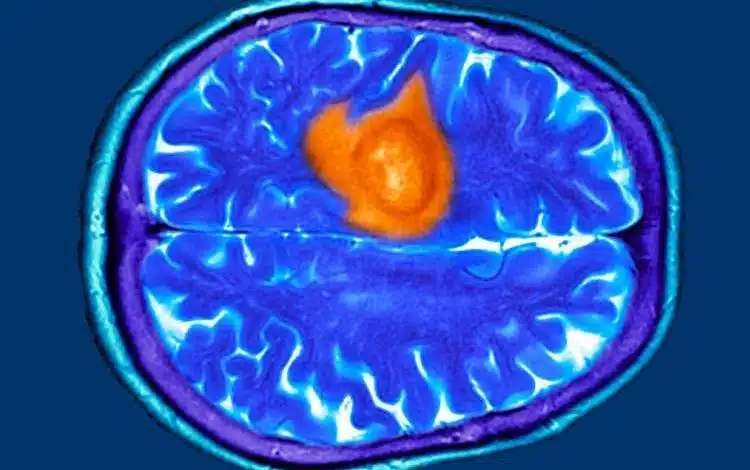

هفت نشانه پنهان تومور مغزی که ممکن است آنها را عادی بپندارید

به گزارش دیتاسنتر من و به نقل از ساینسآلرت، پژوهشهای اخیر نشان میدهد که بیماران و پزشکان عمومی در مراحل اولیه اغلب این نشانهها را نادیده میگیرند و همین امر باعث تأخیر در تشخیص میشود. از آنجا که درمان تومور مغزی در مراحل پیشرفته دشوارتر است، شناسایی علائم اولیه اهمیت ویژهای دارد.

تومور مغزی میتواند با علائمی مشابه بیماریهای رایج مانند اضطراب، عفونت سینوس یا یائسگی بروز کند. در پژوهشی که بر پایه مصاحبه با بیماران انجام شد، هفت علامت اصلی شایع اما فریبنده شناسایی شد. نخستین مورد، دشواری در یافتن کلمات است؛ برخی بیماران در صحبت کردن یا کامل کردن جمله دچار وقفه میشدند، موضوعی که ابتدا به استرس یا خستگی نسبت داده شد. دوم، مهذهنی یا Brain Fog است که با ناتوانی در تمرکز و فراموشی همراه میشود. اگر این حالت با مشکلات گفتاری یا بینایی همراه شود، نیاز به بررسی پزشکی دارد.